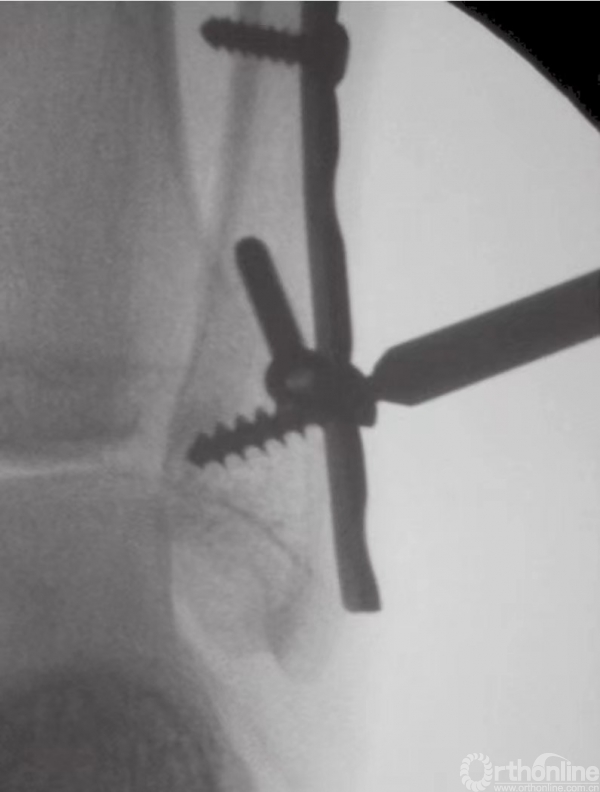

当发生腓骨粉碎时,使用桥形接骨板,从而能绕过碎骨,皮质固定也可在骨折区域上下完成。在用螺钉固定前,应预先描出接骨板的轮廓。有时,如果在很低的位置发生横行骨折,可在踝部用4mm的张力性钢丝带加以固定。术中进行影像学检查,可以极为有效地避免远端的螺钉将关节刺穿(图9)。

图9 置入远端螺钉时应避免穿入关节内